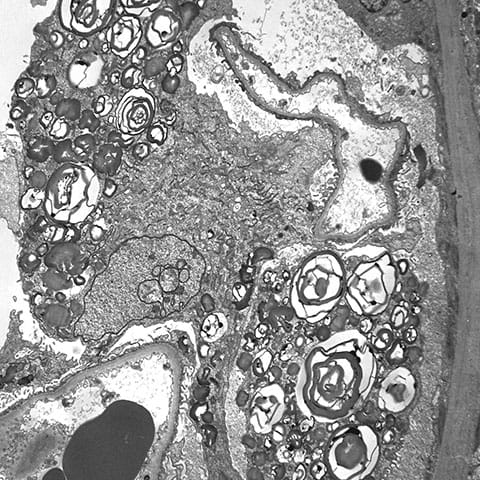

Zebra bodies in Fabry disease